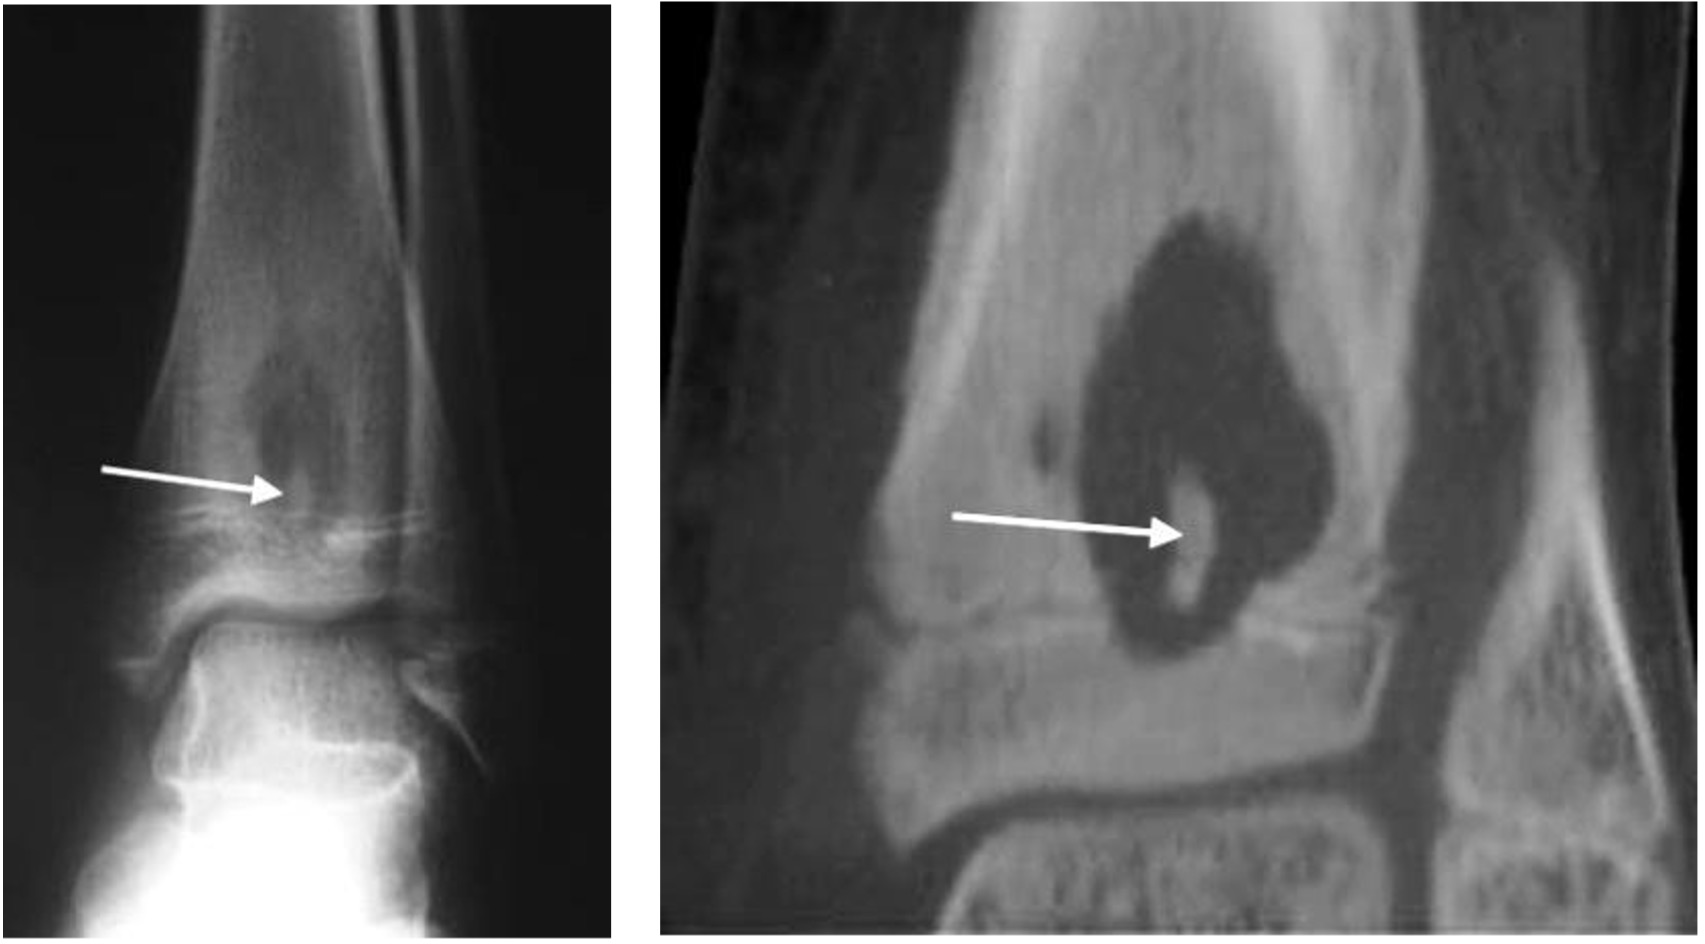

- Focal flattening and compression of talar dome; osteochondral fragment within crater

- Displaced osteochondral fragment with focal concavity of talar dome and intra-articular bone fragment

Osteochondritis dissecans medial talar dome (arrow)